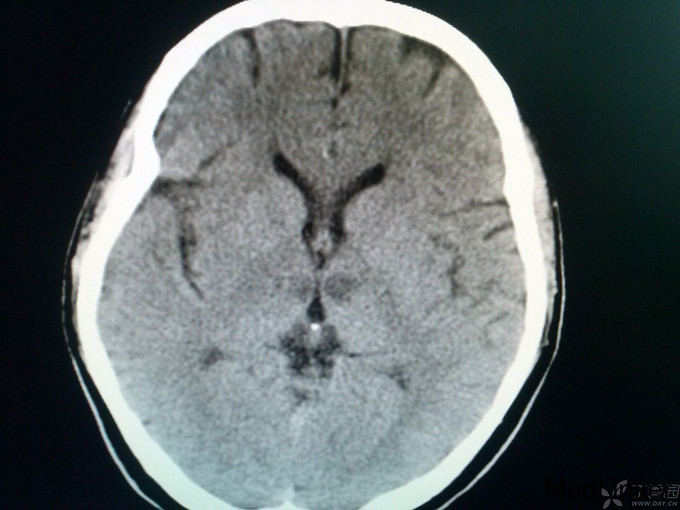

女患 40岁主诉:昏迷3个小时于4月26日入院 现病史:家属代诉患者于今晨7:30左右突然出现走路不稳,数分钟后昏迷,叫不醒,家属呼120来我医院,途中抽搐一次。 既往史:患者13岁时患风心病,04年行主动脉瓣及二尖瓣手术,为机械瓣,之后一直应用华法林1片口服,房颤史不明确,2年前有一过性昏迷症状,未在意。 上传27日CT:

查体:体温36.0℃,脉搏60次/分,呼吸20次/分,血压120/80mmHg。平车推入病房,查体不合作。皮肤巩膜无黄染,胸前见手术瘢痕,双肺呼吸音粗,未闻及罗音,心室率72次/分,律绝对不齐,无病理性杂音,腹部膨隆,膀胱区叩诊为浊音,肝脾肋下未触及。神经系统专科查体:嗜睡,双瞳孔同大同圆,双眼直径3.0mm,对光反射灵敏,双侧鼻唇沟对称,咽反射(+),四肢对疼痛刺激有反应,肌张力正常,肱二头肌、肱三头肌肌腱及膝反射、跟腱反射均亢进,病理征:Babinski征L(+),R(+),颈无抵抗,Kernig征(-)。头CT:未见异常;入院后给予甘露醇125毫升间隔12小时静点一次,呋塞米20毫克间隔12小时静点一次。给予华法林2.5mg日一次口服、奥扎格雷80mg日一次静滴、活血化瘀、营养神经治疗。如是您是首诊患者,有何不同治疗方案?双抗+华法林、稳定斑块合适吗?理由呢? 4月27日: 患者嗜睡,叫醒后,问话能正确回答,患者不能识别物体的形状,左右肢体能识别,查体:嗜睡,双瞳孔同大同圆,双眼直径3.0m,对光反射灵敏,双侧鼻唇沟对称,咽反射(+),四肢活动可,肌张力正常,肱二头肌、肱三头肌肌腱及膝反射、跟腱反射均亢进,病理征:Babinski征L(+),R(+),颈无抵抗,Kernig征(-)。今日复查头CT:后续提供。同时华法林改为3.75mg日一次口服。病灶进展?还是? 4月28日 患者嗜睡,叫醒后,患者左右肢体失认,失算,尿量尚可,心电监护示:血压:96/70mmHg,心率140次/分,律不齐,血氧饱和度99%,现查体:嗜睡,呼吸平稳,肢体疼痛刺激可动,双瞳孔直径3.0mm,对光反射灵敏,双巴氏征(+)。双下肢无浮肿。给予低分子肝素4100单位间隔12小时皮下注射,患者心室率快,给予西地兰0.2mg静推。病灶进展?还是? 5月1日 患者处于嗜睡状态,但嗜睡时间较前明显缩短,问话可答,但答非所问,看似条理清晰,实则“子无须有”,呈现“虚构现象”,如问“几个孩子”,说“1个”,“男孩还是女孩”,答曰“男孩”,实则没有;问“什么水果”,有时能答对,绝大多数回答错误;但患者说话声调低、音量小,复述正常,心电监护示:血压107/77mmHg,心率89次/分,SPO2:98%,查体:嗜睡状态,丘脑性失语,无面瘫,双瞳孔直径3.0mm,对光反射灵敏,双眼上视、下视受限,以下视明显,四肢肌力5级,肌张力正常,双巴氏征(+)。 4月29日CT: